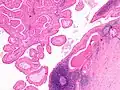

The appearance of this tumor under the microscope is unique. There are cystic spaces surrounded by two uniform rows of oncocytes, which are epithelial cells with abundant, granular, eosinophilic cytoplasm.[7] The cystic spaces have epithelium referred to as papillary infoldings that protrude into them. Additionally, the epithelium has lymphoid stroma with germinal center formation.

This Warthin's tumor presented as a parotid mass in a middle-aged male, who underwent superficial parotidectomy. The tumor, at the right of the image, is well-demarcated from the adjacent parotid tissue and tends to shell out from it.

Low magnification micrograph of a Warthin tumor arising from the parotid gland.

Histopathology of Warthin tumor in the parotid gland. H&E stain.

Histopathology of Warthin tumor in the parotid gland. Another view of a file "Warthin tumor (1).jpg". H&E stain.